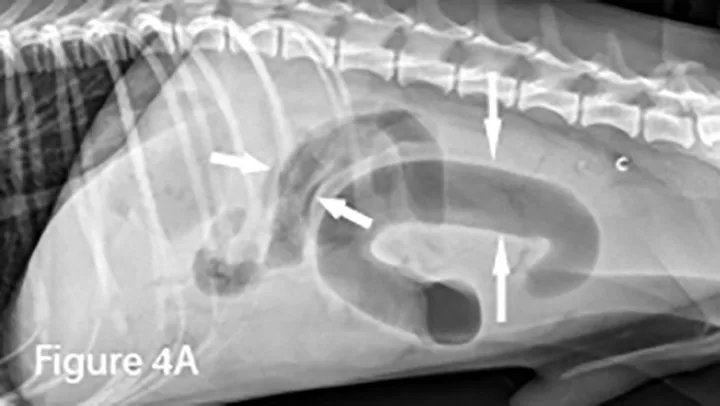

Marked diffuse small intestinal dilation (arrows). (C = colon)

Invagination of 1 portion of the GI tract (intussusceptum) into the lumen of another (intussuscipiens); this is often referred to as the target sign when seen in the transverse plane because of the multiple layers of adjacent intestinal walls.